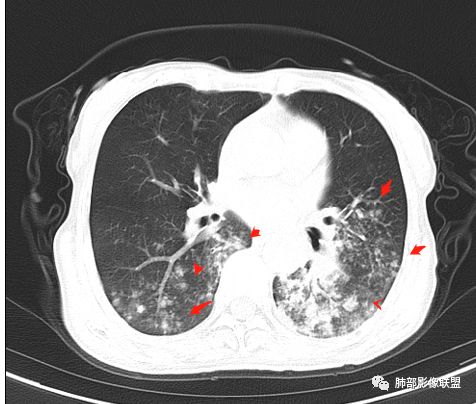

慢性迁延不愈患者 发热伴脓痰 双肺多发小结节伴磨玻璃影 左肺下叶体积缩小 支气管扩张伴实变 实变内支气管不规则 平扫密度尚均较肌肉稍低 支气管扩张感染基础上合并淋巴瘤待查 建议增强穿刺

老年女性,慢性病程,有反复咯血、发热,左下胸廓塌陷,双肺下叶多发片状实变影,伴多发结节,左下肺实变为主伴卫星灶,支气管扩张,伴虫噬样空洞及支气管壁钙化,首先考虑结核,鉴别粘液腺癌

老年丶反复发作2年,但双肺下叶多发腺泡结节,延气道分布,影像不符合陈旧病变,左下实变影,伴牵拉支扩,考虑慢性病变首先考虑吸入性肺炎,建议结合病史是否有隐性误吸,可查胃镜、气管镜丶钡透,除外食管、气管瘘。鉴别腺癌丶放线菌丶努卡菌丶NTM

患者老年女性,反复咳嗽 咳痰 活动后胸闷 气短,胸ct:病变以左肺下叶体积缩小,呈大片实变,实变组织内可见 左肺下叶支气管开口扩张,右肺下叶背段多发结节样病灶,周围有毛玻璃影。良性考虑感染性病变,ABPA ?结核?;恶性考虑:粘膜相关淋巴瘤。

双肺多叶段多发腺泡结节,延气道分布,双下肺为诸,左下肺大片实变影,伴牵拉支扩,老年人首先考虑支气管肺炎。鉴别腺癌。

双下肺多发腺泡结节,左肺下叶实变,彭隆,结核伴感染,鉴别结核伴粘液腺癌。

双肺下叶多发片,结节,左下肺实变,局部膨隆,粘液腺癌?鉴别结核。

晨读病例,老年女性,病程长,左侧胸廓缩小,双下肺叶多发片状实变影,伴多发结节及树芽征,左下肺实变,有坏死空洞,支气管扩张壁增厚有钙化,考虑结核,鉴别粘液腺癌,淋巴瘤,排除异物

病灶位于中下肺部,左下叶应该是源头,其余是播散灶

大家看看这支气管

这些支气管扩张

支气管扩张、扭曲成团,附近钙化灶

这例左下叶的体积是整体缩小的,左下叶的支气管主干稍微小一点点,然后左上叶的下舌段也有类似的病灶,然后我们看到一团乱的支气管扩张,但它有特点,边缘凹凸不平。那什么样的支气管扩张边缘会如此凹凸不平呢,等我截个图:

首先这幅图支气管很多地方是扭曲的,远端扩张的特别厉害。如果是肿瘤,首先考虑淋巴瘤,因为支气管可直达远端,稍扩张,但是它的前提是周围要实性占位的,而且它不会这样扭曲变形。我们看这个病例的支气管扩张,它支气管扩张占大部分区域,中间稍有些实性的结构,这就不符合了。这幅图你会发现所有支气管都是扩张的,实性部分偏少,外围胸水。所以我更倾向慢性炎性病变,能够引起支气管扩张的炎性病变有哪些?结核?NTM?支扩伴感染?大方向是慢性炎性病变。这些左下肺播散出来的病灶,咳中等量黄浓痰,我考虑还可能合并细菌感染。

1.双肺斑片影、大小不等结节影,边界不清,密度较均一,钙化不多见,可见树丫。

2.左肺下叶大范围病灶,其间柱状支气管扩张相当显眼。

这些都支持慢性炎性改变。

3.我们知道继发性肺结核为典型的慢性消耗性疾病,较少出现高热及较大量浓痰。该患者病灶密度较均一,新旧不等的特点并不突出,缺少高密度区,双肺上叶比较干净,夸张的支扩也有别于结核病灶导致的“鸡爪样”改变。